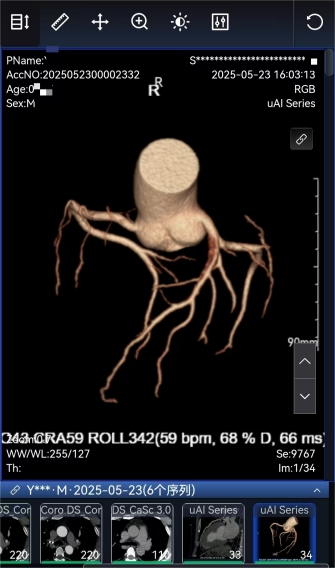

排栓前:左前降支近段管腔约中—重度狭窄 排栓后:到医院检查不符合心脏支架标准